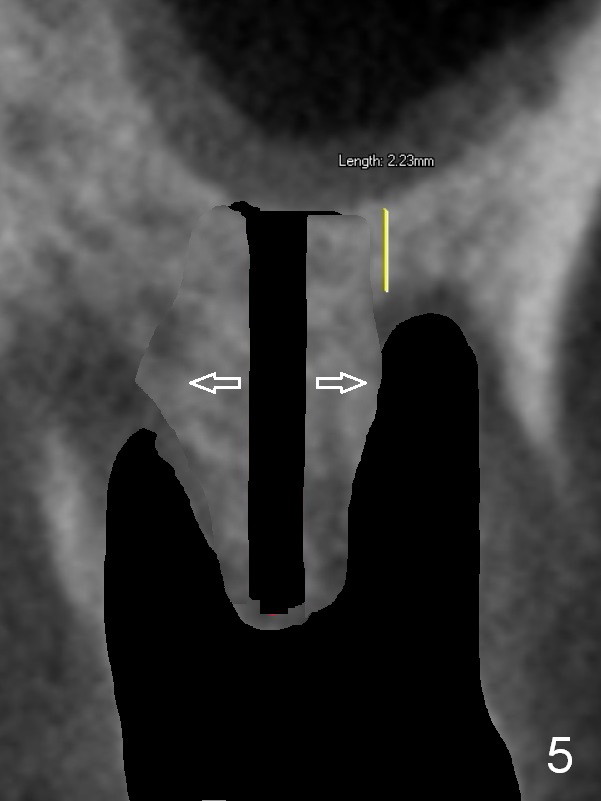

Preop CT shows that the septum appears to be able to hold a 11 mm long implant (Fig.1 sagittal section). There are periapical radiolucent lesions of the buccal (Fig.2 (coronal section) B) and palatal roots; bone height above the buccal apex is ~ 2 mm (Fig.3). When the tooth #14 is extracted, a 1.6 mm pilot drill is used to start osteotomy in the middle of the fairly thin septum (Fig.3 red line, Fig.4 S). It is hoped that Magic Expanders (ME) can enlarge the osteotomy by pushing the buccal and palatal bone plates of the septum outward (Fig.5 arrows).

The septal bone is dense and the osteotomy is enlarged by alternating use of drills and expanders. By the time 3.8 mm ME is tapped in (Fig.6), the buccal plate of the septum is perforated. The ME is stable, in spite of the fact that it is only supported by 2-3 mm bone buccally (Fig.7). Continuously alternating use of MEs and drills leads to placement of a 5x11 mm implant with 30 Ncm insertion torque and sinus lift. After placement of bone graft (Fig.8 *) and 5x4(3) mm pair abutment (A), an immediate provisional is fabricated. Red dashed lines in Fig.6,9 represent the mesial outline of the socket, whereas black dashed in Fig.6 sinus floor. It suggests that the implant is stabilized by relatively small amount of native bone. Although IBS implants have aggressive thread patterns, a proper apical osteotomy should be prepared in the depth (perforates the sinus floor in this case) and diameter (4.3 mm drill) prior to placement.